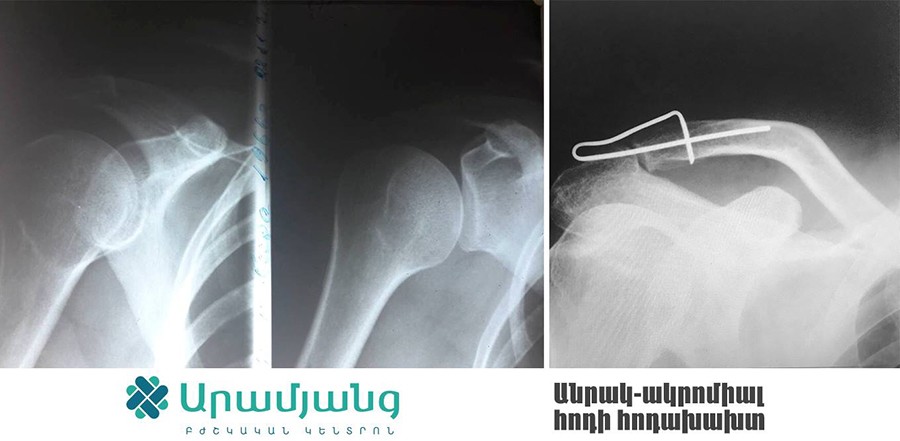

Արամյանց բժշկական կենտրոնի Օրթոպեդիայի ու Վնասվածքաբանության բաժանմունքում սկսել են իրականացնել բացառիկ վիրահատություններ հիշողություն ունեցող հատուկ մետաղի կիրառմամբ: Մետաղի օգտագործումն առավել արդյունավետ է դարձնում կոտրվածքների բուժումն ու պացիենտի արագ ապաքինումը:

Արամյանց Բժշկական կենտրոնի փոխտնօրեն, վնասվածքաբան-օրթոպեդ Միքայել Բուռնուչյանի խոսքով՝ սառեցնելով 0-5 աստիճան՝ այս մետաղը հնարավոր է ծալել ու կիրառել ցանկացած դիրքով՝ կախված կոտրվածքի տեղակայումից: Հետո այն մարմնի ջերմության ազդեցությամբ 37-40 աստիճանում կվերադառնա իր նախնական  դիրքին՝ ապահովելով ոսկրաբեկորների կոպրեսիան:

Մետաղն իր արդյունավետությամբ կարող է փոխարինել նմանատիպ վիրահատությունների ժամանակ կիրառվող մետաղալարին և պտուտակին: Այն իր մեջ պարունակում է ուժ, որն էլ հենց ոսկրաբեկորները պահում է մշտական կոմպրեսիայի վիճակում. արդյունքում ոսկրացման ընթացքն ավելի է արագ է տեղի ունենում: Այն որոշ դեպքում կարելի է կիրառել անգամ Իլիզարովի ծանր ու խոշոր ապարատի փոխարեն՝ազատելով պացիենտին լուրջ անհարմարությունից:

Ընդ որում, մետաղը տեղադրելու համար պետք է ընդամենը քիչ ինվազիվ և փոքր միջամտություն կատարել: Մետաղը առաձգական է և ամուր, այն նիկելի և տիտանի խառնուրդ է, ունի տարբեր չափսեր ու ձևեր, որոնք կիրառվում են ըստ դեպքի ու ցուցումի:

Հիշողություն ունեցող մետաղը կիրառվում է  և´ թարմ կոտրվածքների, և´ կեղծ հոդերի, և´ ոչ ճիշտ սերտաճած կոտրվածքների, և´ չսերտաճող կոտրվածքների ժամանակ: